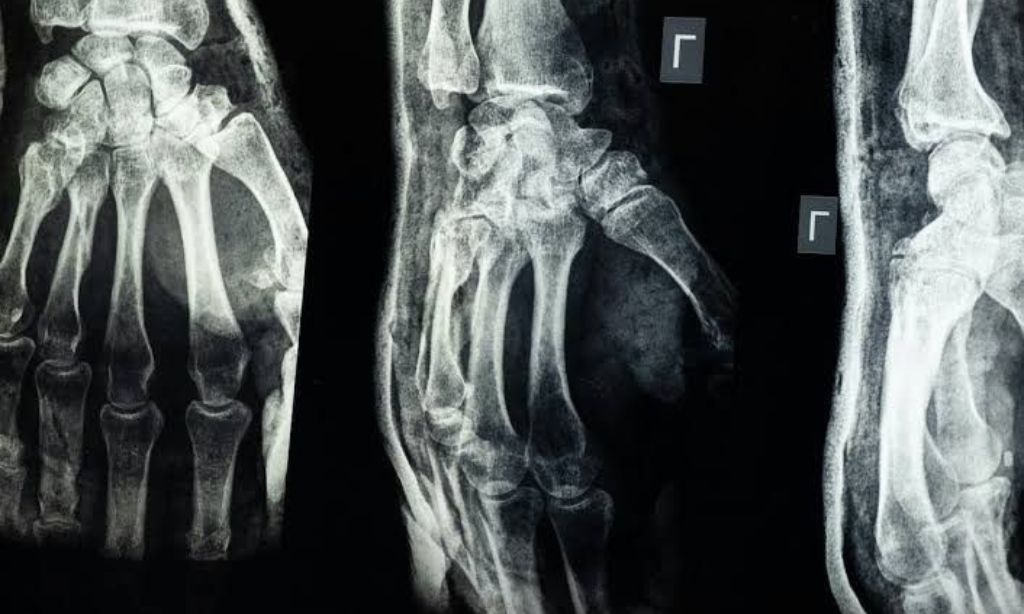

In kontrollierten Studien zeigte Bone-02 eine ungewöhnliche Stärke: Eine Scherkraftwiderstandsfähigkeit von mehr als einer halben Megapascal und eine Druckfestigkeit, die der von natürlichem Knochen vergleichbar ist. Direkt auf die Bruchstelle aufgetragen, stabilisiert er zersplitterte Fragmente innerhalb von Minuten – sogar bei komplexen komminutierten Frakturen, bei denen Knochen in mehrere Stücke zerbrechen.

Mehr als 150 Patienten in China haben die Behandlung bereits erhalten. Ein junger Fabrikarbeiter mit einem stark zersplitterten Handgelenk stand vor der Aussicht auf umfangreiche Operationen und Monate eingeschränkter Mobilität. Stattdessen verwendeten die Chirurgen Bone-02 durch einen zwei Zentimeter langen Einschnitt; innerhalb von drei Monaten hatte er die volle Funktion wiedererlangt, ohne Komplikationen.